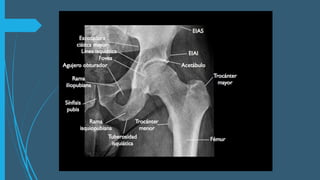

ANATOMIA

 LIGAMENTOS  ESTABILIZADORES Extraarticulares •Ligamento ileofemoral • Ligamento pubofemoral • Ligamento isquifemoral Intraarticulares • Ligamento de la cabeza del femur • Ligamento transverso